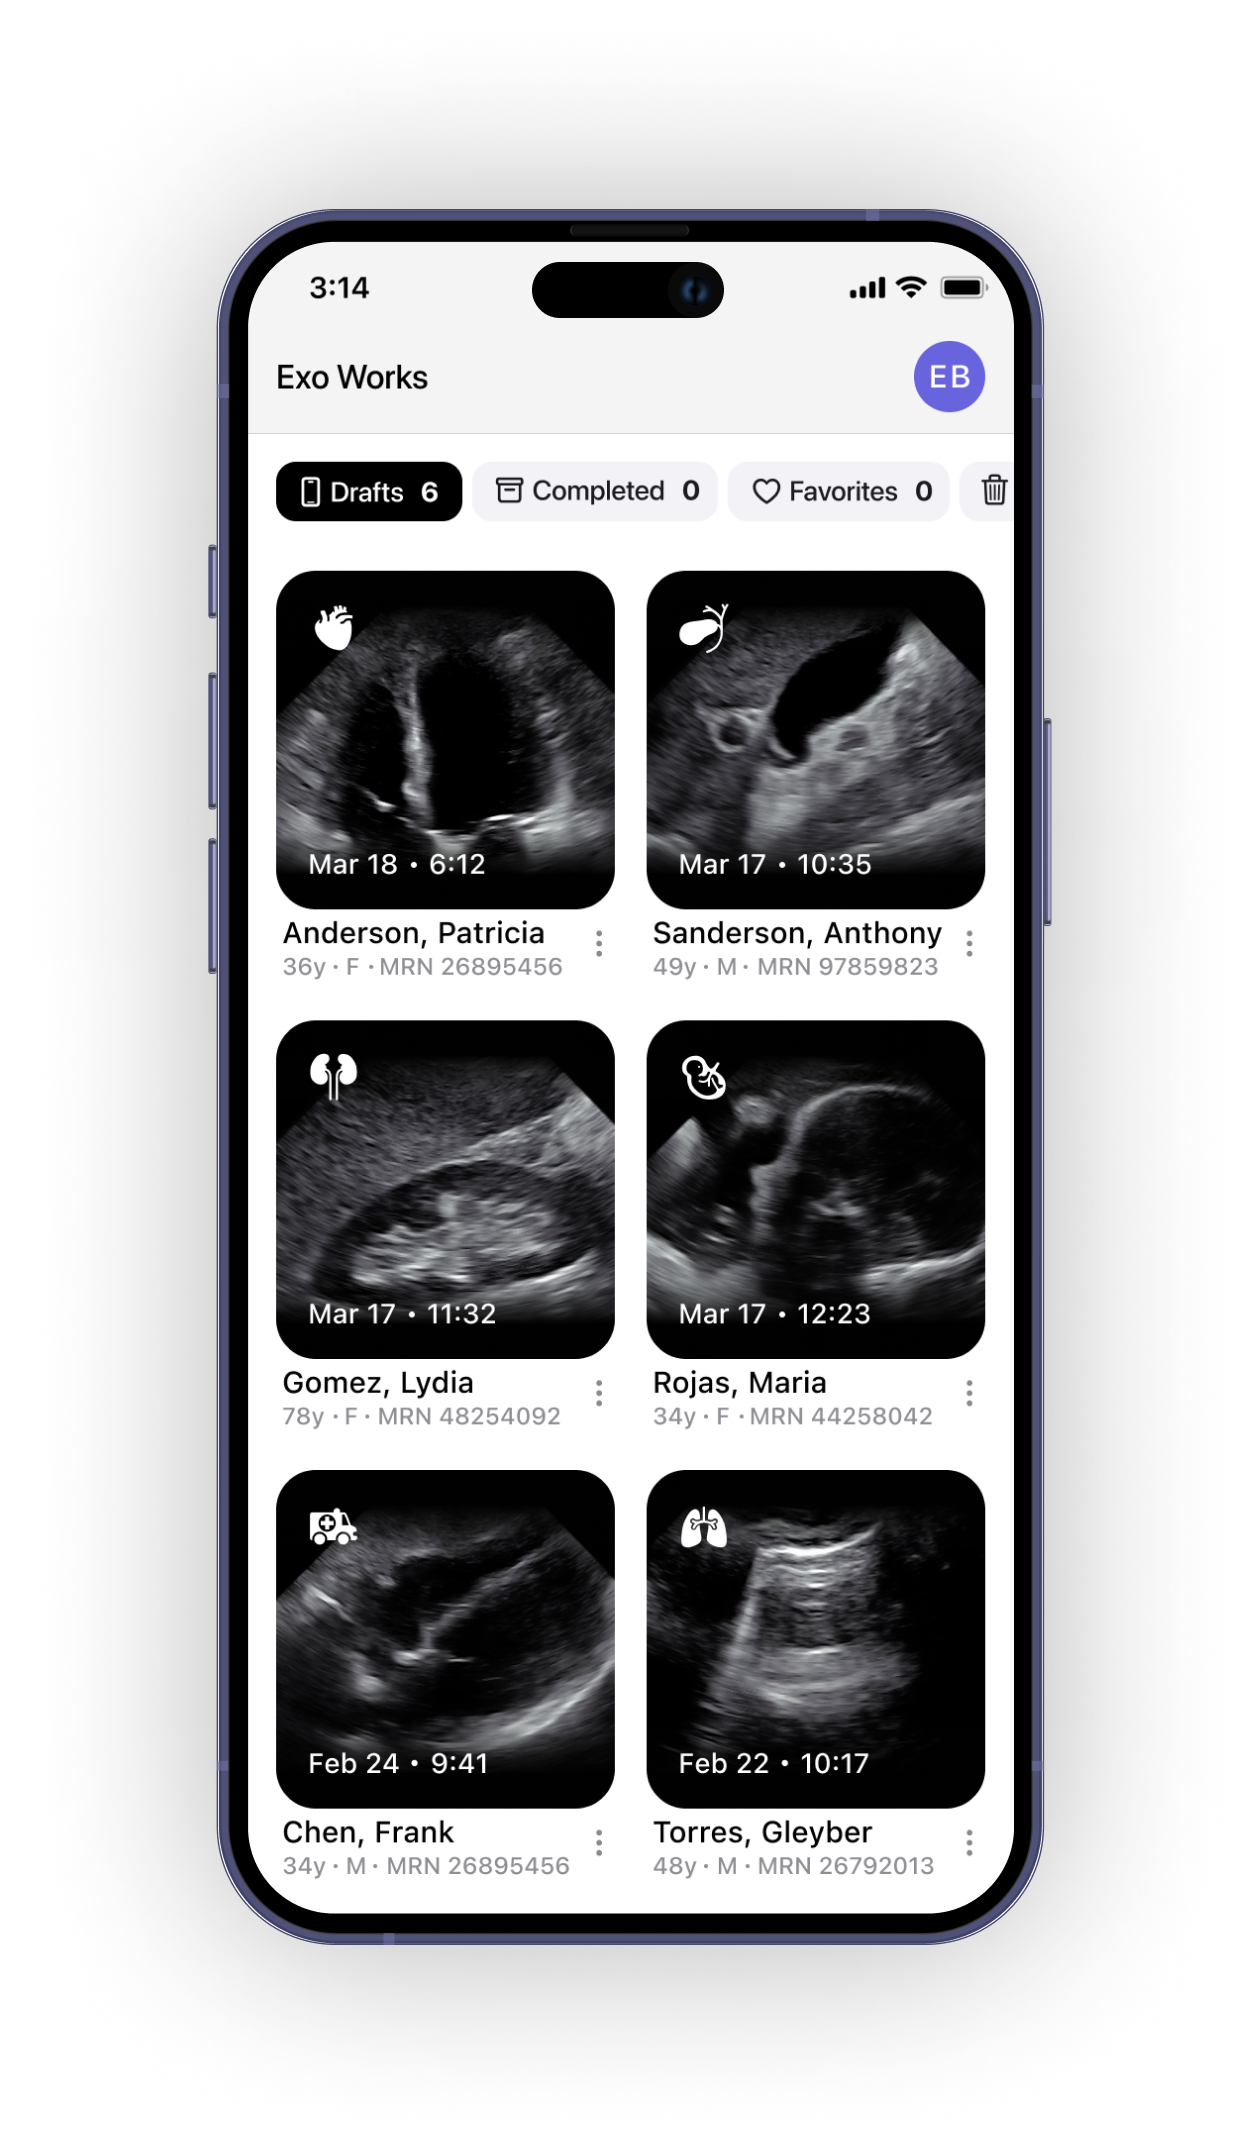

AI and Workflow

Exo Iris blends imaging with powerful on-device, real-time AI and workflow software so you have instant answers at your fingertips.

Core AI

SweepAI™: Cardiac, Lung, IVC

Workflow

22 worksheets for documentation compliance

Anonymized image and exam sharing

DICOM

Modality worklist, store, send

Integration

Modality Worklist

PACS/VNA

EHR**

Storage

1 TB on Exo cloud